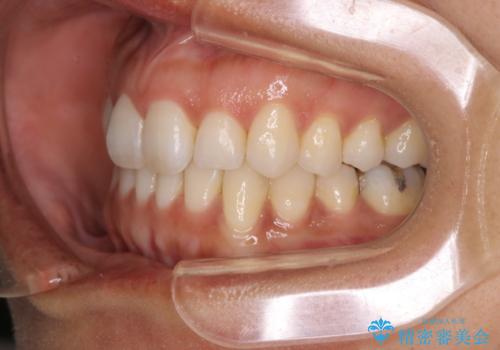

【インビザライン】前歯をきれいな歯並びにしたい

- 前歯の叢生を主訴に来院されました。このケースは抜歯をせずにIPRにてスペースを確保し、並べる計画をたてました。

きちんと使用時間を守って使用していただいたことで短い期間で治療が終了しました。